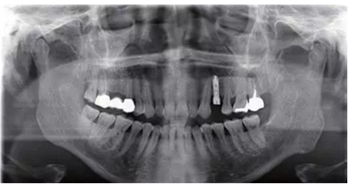

種植完成

種植完成后可以通過拍攝曲面體層或是根尖片來確認(rèn)種植體的植入情況,并作為資料加以保存。

種植手術(shù)完成2周后進(jìn)行拆線??梢钥闯鲕浗M織愈合良好。

圖7 曲面體層片